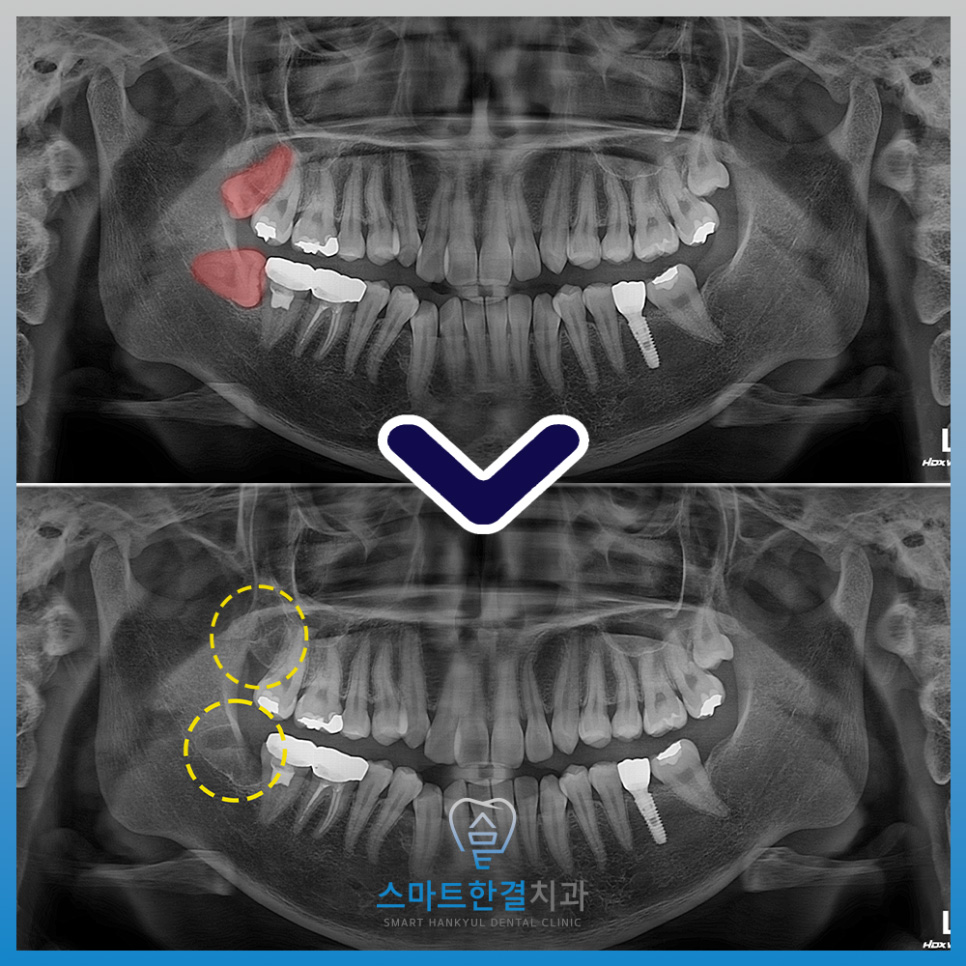

사랑니 발치 전후 모습입니다!

주변 치아 및 조직에 손상 없이

깨끗하게 발치를 한 모습이에요.

아래쪽 사랑니는 누운 상태로 매복되어 있어

잇몸을 절개한 후 치아를 분할하여

발치하는 방식으로 진행하며

위쪽도 같이 진행하였는데요.

특히 사랑니와 밀접하게 맞닿아 있는 인접 치아는,

사진에서 보시듯 이미 치료를 받고

크라운 보철물이 씌워진 상태였어요.

이러한 경우, 발치 과정에서

크라운 탈락이나 손상이 발생할 수 있기 때문에

인접 치아에 물리적 압력이 전달되지 않도록

세심한 술식과 충분한 시야 확보를 통해

주의 깊게 발치를 진행하였답니다.